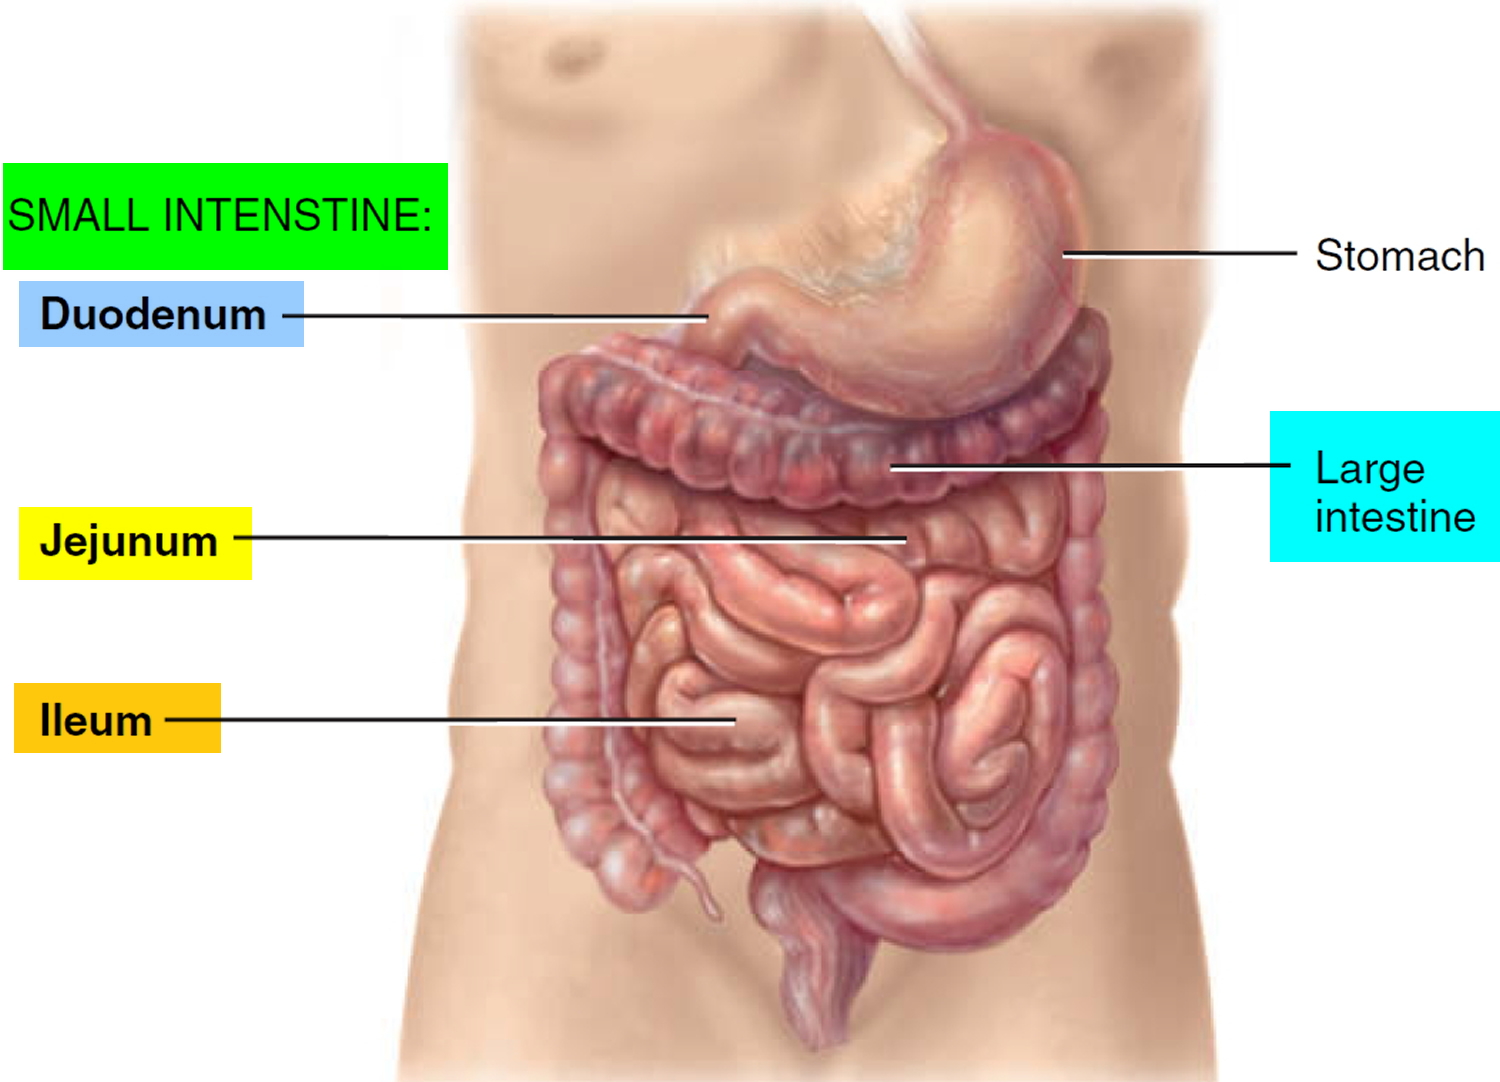

Bowel Obstruction Intestinal Obstruction MedlinePlus

Intestinal Obstruction

Intestinal Obstruction

Intestinal Obstruction